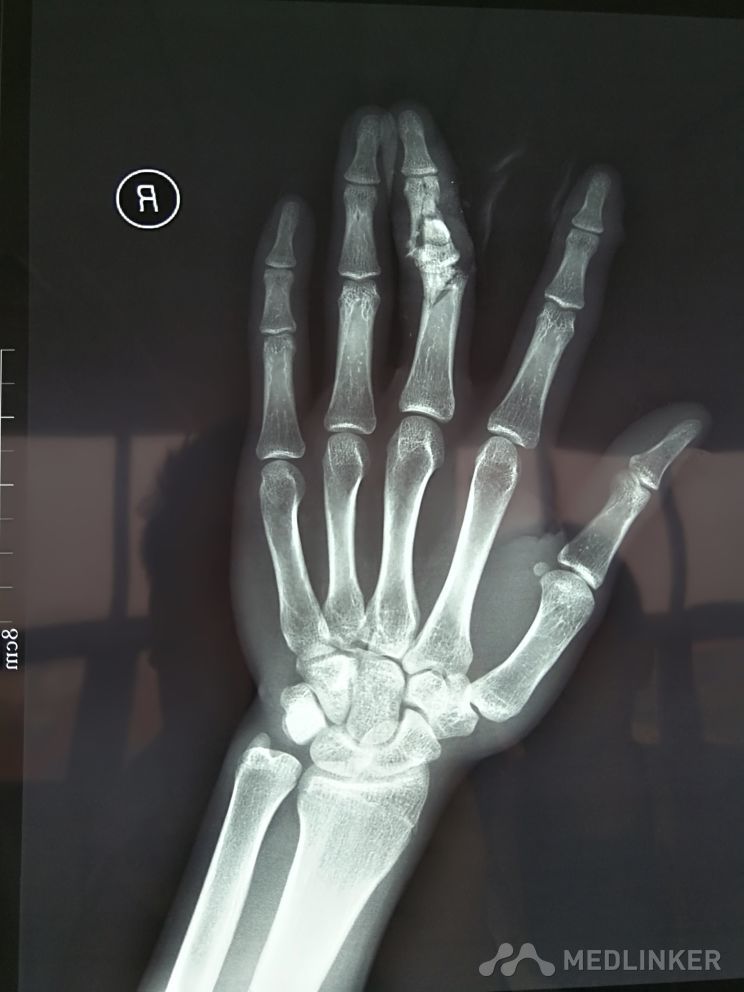

手指粉碎性骨折

患者机器碰伤,导致中指粉碎性骨折,关节面毁损。